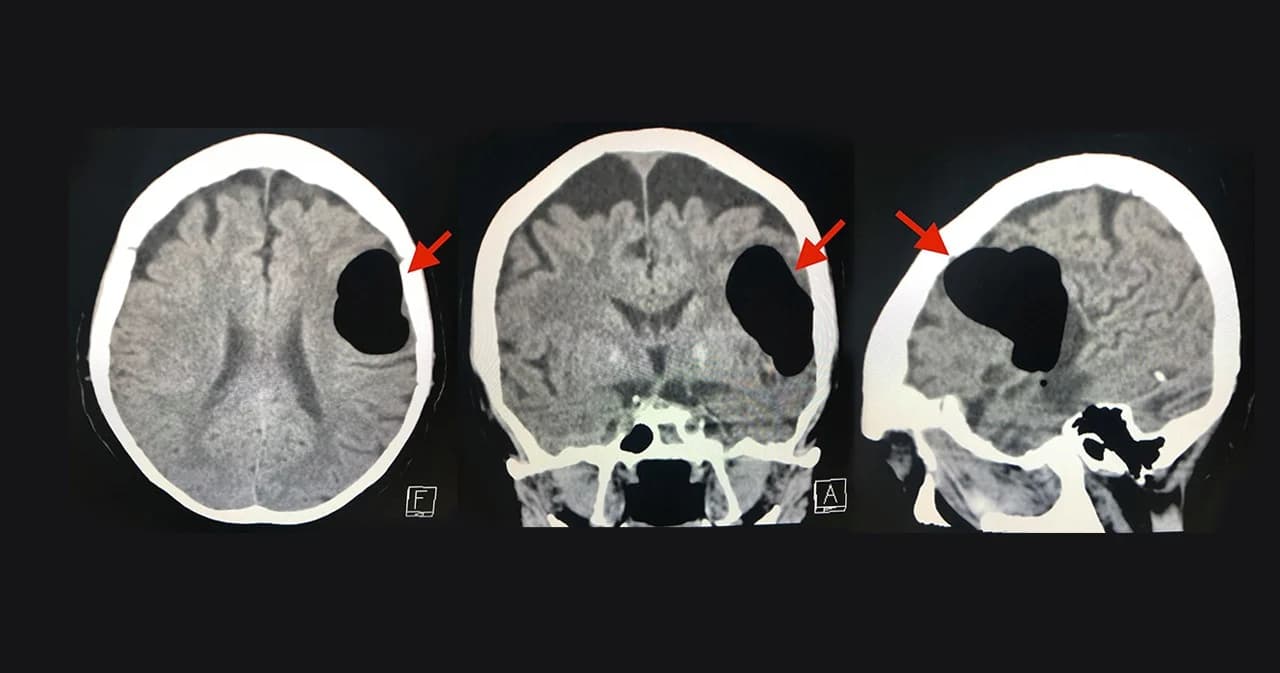

วันที่ 14 พฤษภาคม 2563 ผู้ป่วยกลับมารพ.อีกครั้งหลังจากจามแล้วเอามือปิดปากปิดจมูกเพราะไม่อยากให้มีเสียงดัง หลังทำมีอาการพูดไม่ชัด หน้าข้างขวาเบี้ยว หูข้างซ้ายอื้อ มีเสียงดัง ทำคอมพิวเตอร์สมองพบลม (air pocket) ในเนื้อสมองข้างซ้ายขนาด 5.1 × 4.1 × 2.8 เซนติเมตร (ดูรูป) ตำแหน่งเดิมเหมือนเมื่อ 3 ปี 5 เดือนก่อน แต่ปริมาตรของลมในเนื้อสมองครั้งนี้น้อยกว่า ผู้ป่วยนอนในโรงพยาบาล 4 วัน อาการดีขึ้นช้าๆ กลับบ้านได้